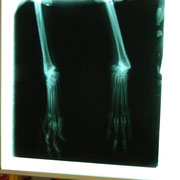

Voici les première infos que nous avons : La galga de La Melgosa, elle a 3 ans et s'appelle Reata sur son passeport... voyez vous-même comment elle était... le galguero l'a donnée à un autre qui à son tour l'adonné à un berger de La Melgosa, la chienne est toujours au nom du premier et a causé un accident de la route..... Regardez ses pattes... traumatologue va les étudier, pour l'instant, on voit un fracture du radius et des poignets, mais ça fait plus d'une semaine, on ne sait pas ce qui pourra être fait...

Le chirurgien, à la vue des radios est optimiste! ;o)